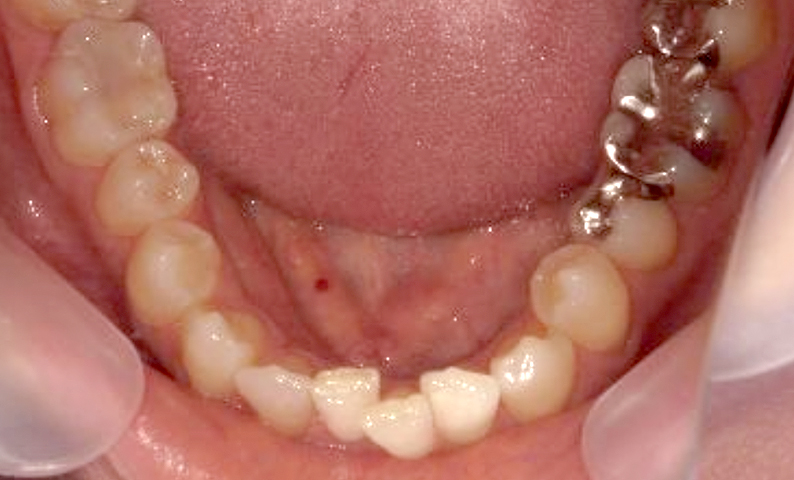

症例_002 上顎だけの部分矯正

治療期間:7ヶ月金額:30万円+税女性前歯のガタガタ上の前歯だけ

| Before | After |

|---|---|

|